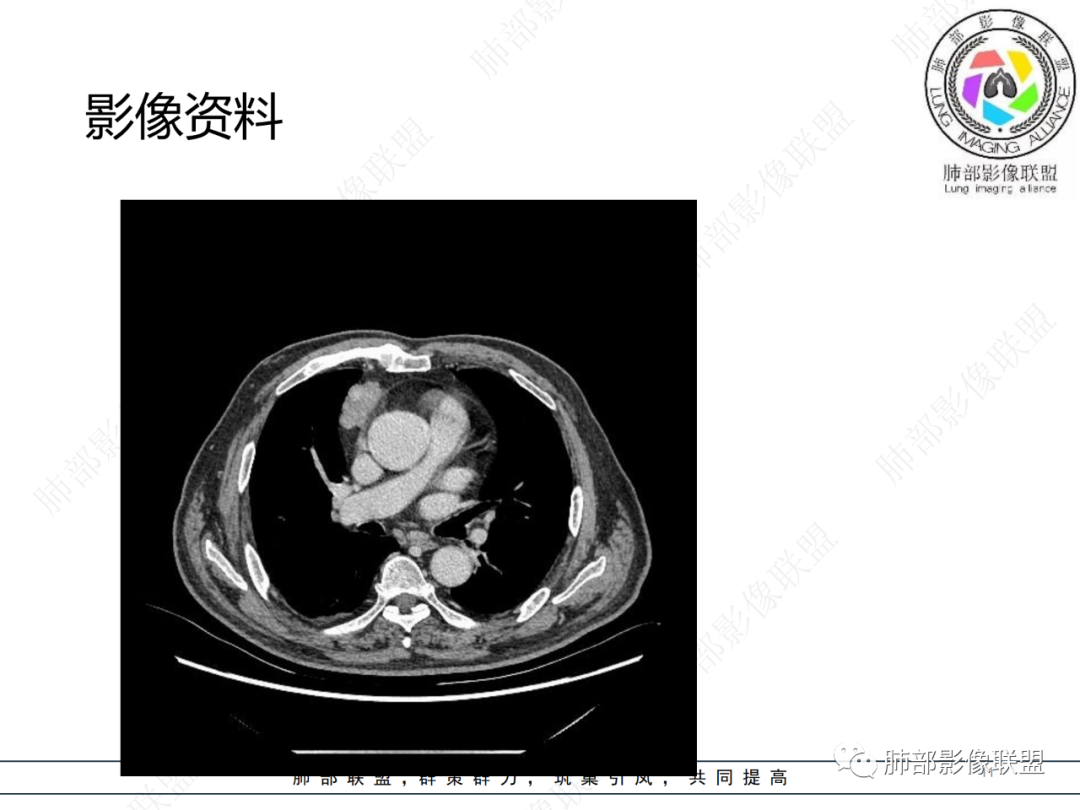

老年男性,体检发现纵隔占位,胸部CT检查所见,前纵隔多发软组织结节或肿块,右侧胸膜结节,密度均匀,边缘分叶,未见明显坏死,强化尚明显均匀强化,冠状位第1张图,左侧膈肌连续性中断,未见明确脾脏显示,可以考虑转移?异位组织(异位脾脏)?如果左侧膈肌确实断裂且无脾脏那么考虑异位脾脏可能大,或者代偿的淋巴结,再有鉴别神经源性肿瘤,入鞘瘤,不过鞘瘤一般会有ab区,这个病例没有。

右前纵膈不规则软组织密度影,密度均匀,分叶,中度强化,心包受侵,右侧胸膜不规则结节,明显强化,考虑胸腺瘤B2或B3型伴胸膜转移,鉴别胸腺癌

老年男性,前纵隔软组织结节灶,分叶状,偏于右侧,右侧胸膜亦可见结节灶,考虑高危型胸腺瘤或胸腺癌侵及胸膜

老年男性,右前纵隔结节,右侧胸膜下小结节,增强前纵隔结节中度欠均匀性强化,首先考虑胸腺瘤(B2、3级),鉴别纵隔神经内分泌肿瘤,比如类癌。

男,76岁,前纵膈偏右结节,形态较规则,浅分叶,富血供,增强明显不均匀强化,强化峰值在动脉期,考虑B2,3胸腺瘤,鉴别胸腺类癌(一般强化峰值在静脉期),胸腺鳞癌(形态不规则,边缘不清晰,多侵犯邻近大血管)

肺盟病例,右前纵膈占位,边缘有钙化,强化显著,临近心包有少许积液。考虑胸腺类癌可能,右肺胸膜下病灶考虑炎性肉芽肿可能。